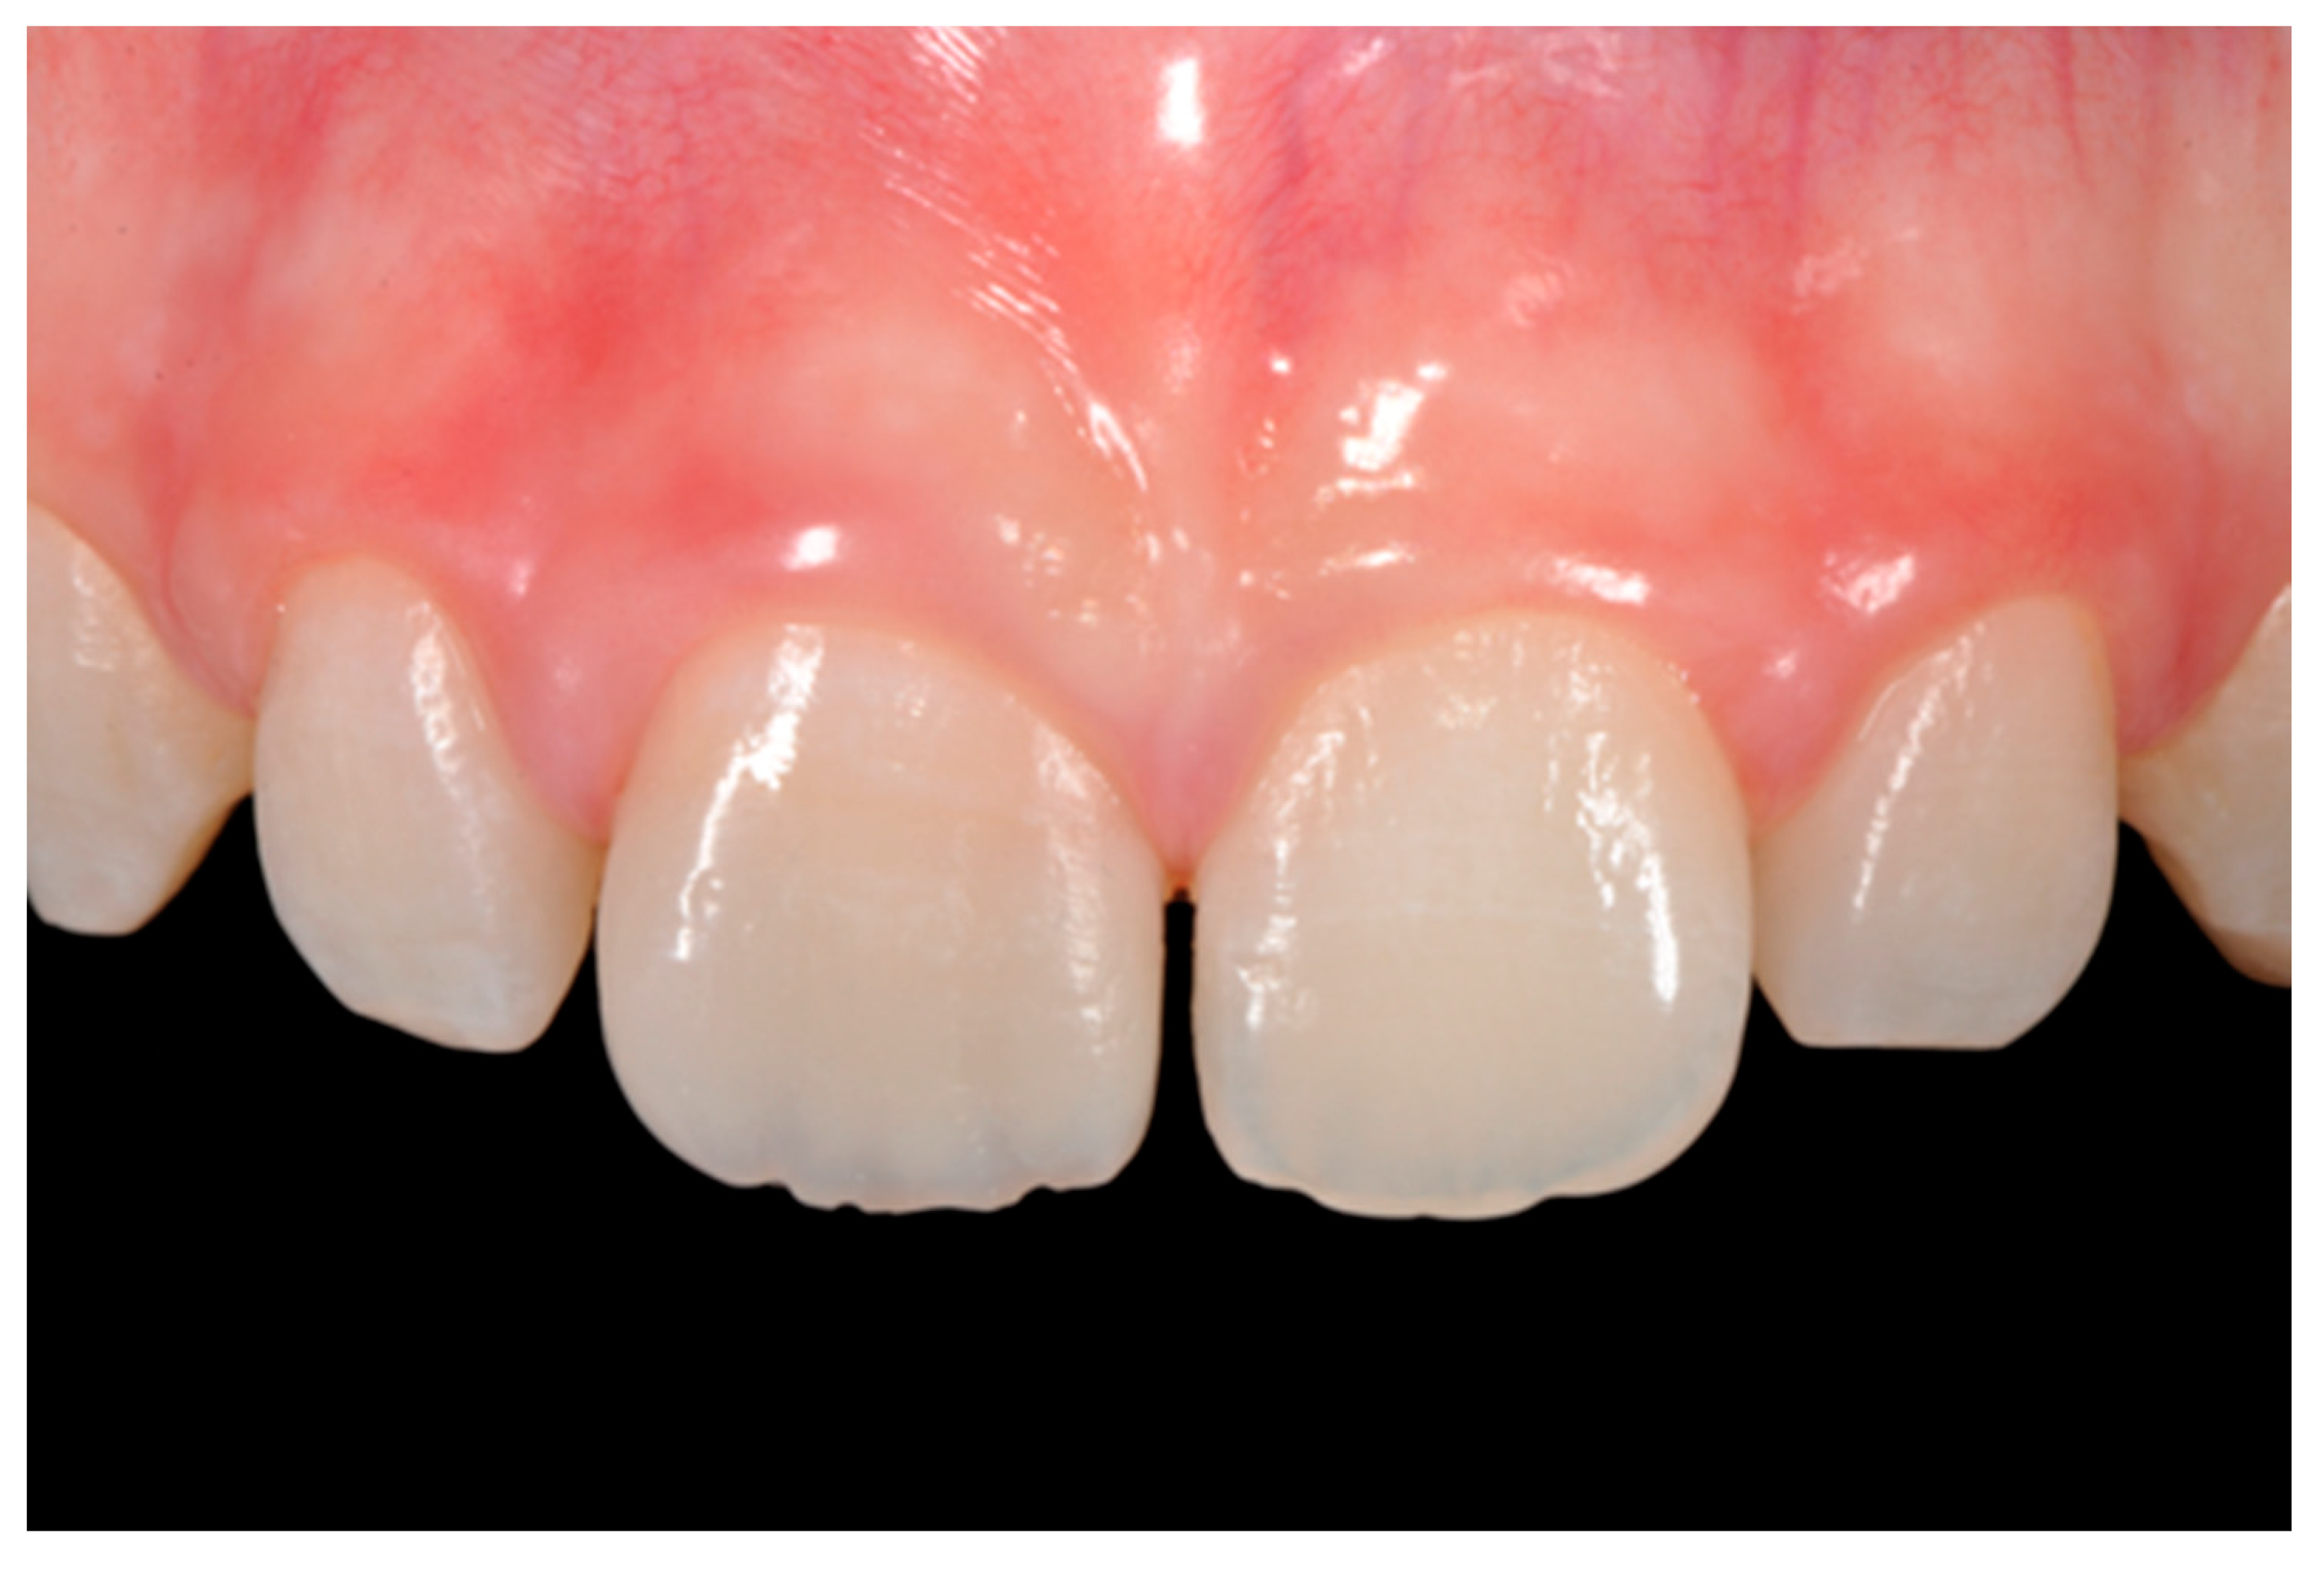

Figure 15.

Three months post-operative. Reprinted from Restauri diretti nei settori anteriori, G. Paolone, S. Scolavino, © 2021, with permission from Quintessence Publishing Italy.

Figure 16.

One year post-operative. Reprinted from Restauri diretti nei settori anteriori, G. Paolone, S. Scolavino, © 2021, with permission from Quintessence Publishing Italy.